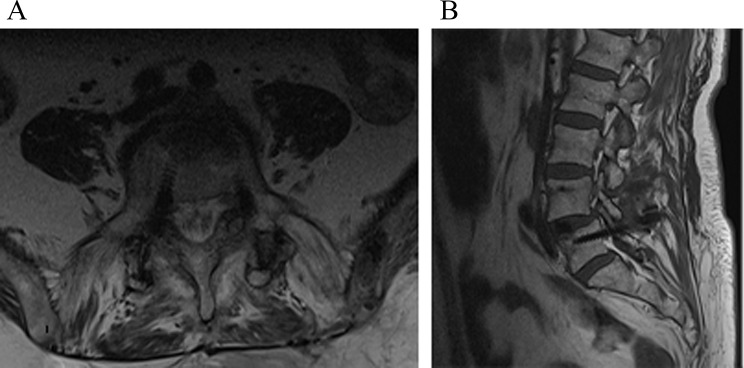

Fig. 3.

Axial and sagittal views demonstrating the medial positioning of the right L5 pedicle screw following revision surgery. (A): Axial view showing the medial deviation of the right L5 pedicle screw. (B): Sagittal view illustrating the screw’s position outside the pedicle